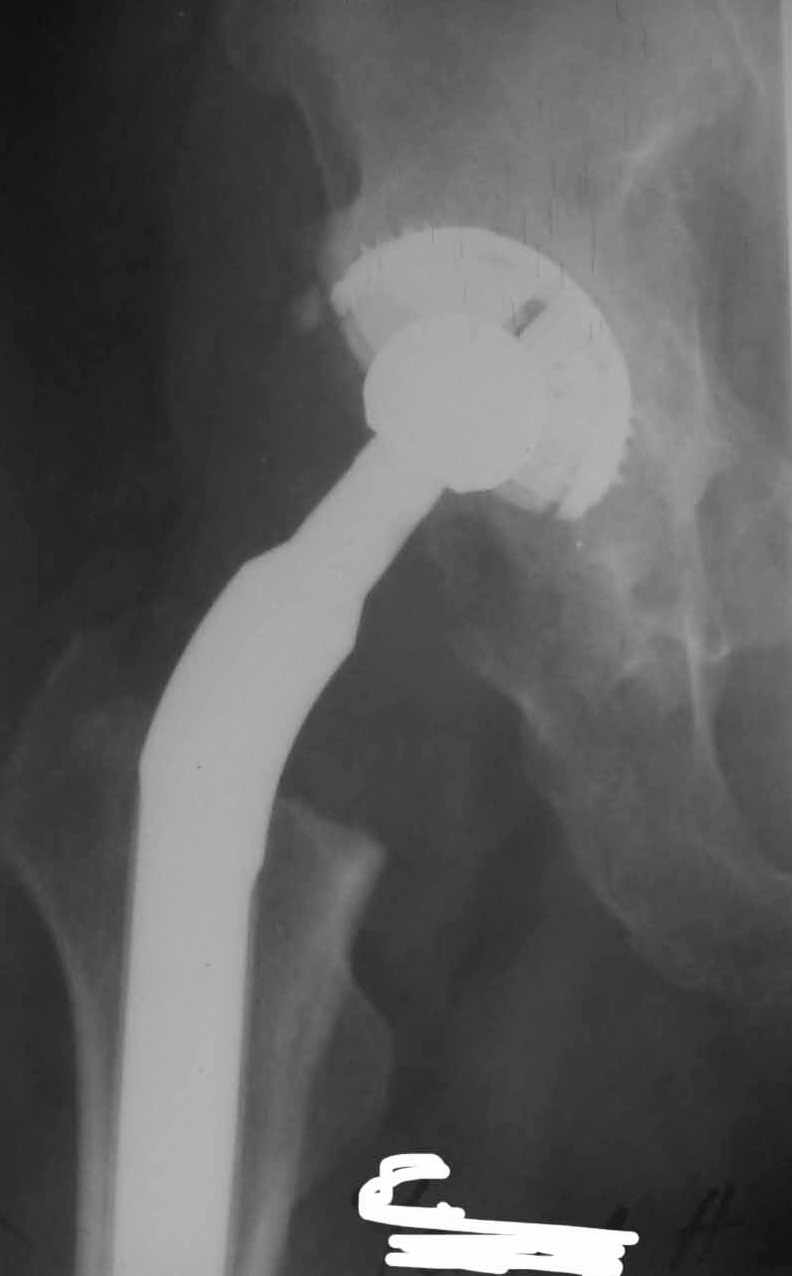

Во вложении - рентгенограммы после вывиха и после вправления.

Идея очень простая, в случае, если удасться прожить без вывиха 2.5-3 месяца, вероятность его возникновения в будущем значительно уменьшится. Оптимальный вариант - повторная иммобилизация на срок 6 недель с нагрузкой на ногу (как бы я ни не любил гипс, но этот путь проверенный и может дать результат). Если это невозможно, то исключительно осторожная реабилитация под строгим контролем без резких движений (спать в положении на спине с отведением и подушкой под коленкой и т.д.). Ходьба сама по себе не опасна, опасен переход от положения "лежа" в положение "полусидя" и "стоя" и наоборот.

1. AP X ray of the Pelvis is a must. It will likely show that right hip/ femur is longer than left. Even based on Rt Hip AP X Ray it is my impression.